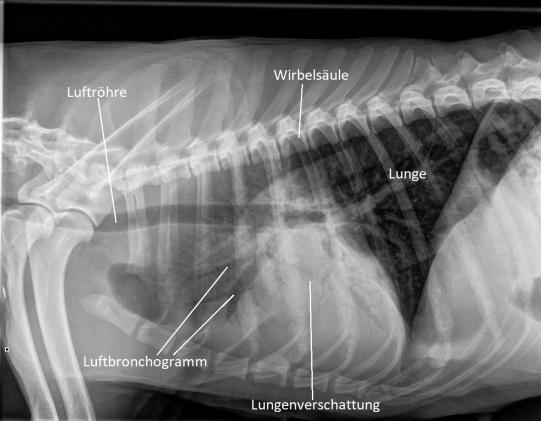

Leider bessert sich Asky's Zustand nicht wirklich, und die Hündin wird erneut vorgestellt. Nun werden Lungenröntgen angefertigt, die das ganze Ausmass des Problemes ans Licht bringen: Weite Teile der Lunge des Hundes erscheinen auf dem Röntgenbild weiss - hier ist die Luft durch Flüssigkeit oder Gewebe ersetzt worden. Wie Bäume im Nebel sind auch sogenannte Luftbronchogramme sichtbar - nur die grossen Bronchien enthalten noch Luft. Ganz offensichtlich hat sich Asky eine fulminante Lungenentzündung geholt!